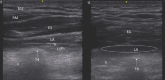

Figures